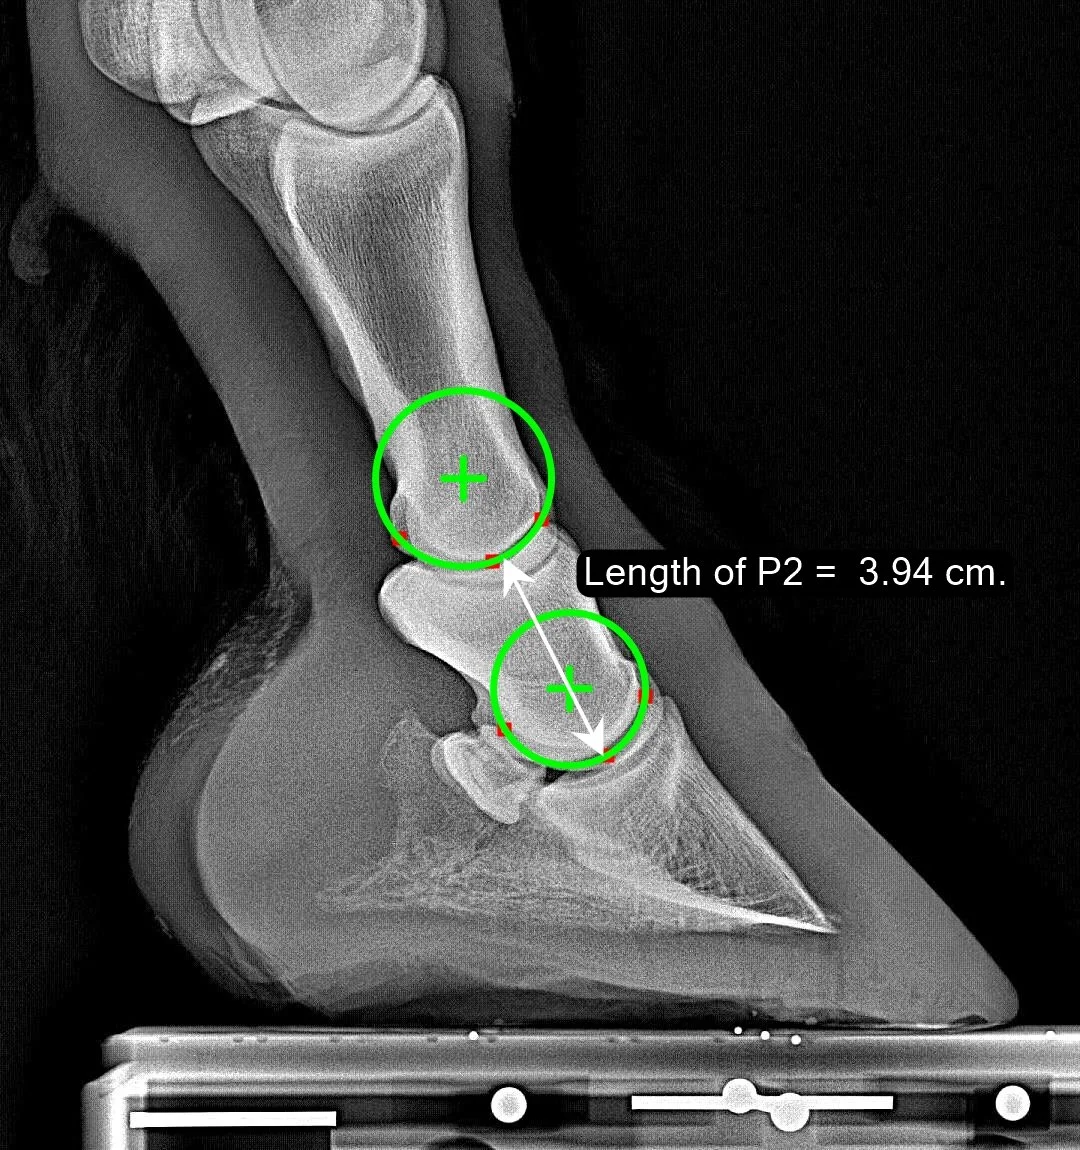

Length of P2

The Length of P2 is used in our system to scale any linear measurements to remove the dependence on hoof size. This way, we can make statements like “it is normal for the P3 Descent value to be 22% of the length of P2.” Note that the length of P2 as we have defined it is unaffected by the stance of the horse and is unaffected by trim alterations to the hoof. The precise definition is: measure the distance between rotation centers of the pastern and coffin joints, then add the radius of the coffin-joint circle and subtract the radius of the pastern-joint circle. The result (drawn in white below) is the ‘Length of P2’.

Normal Range

The 15% wings of our distribution graph are not colored red for this parameter, as there nothing wrong with being a small horse or a large horse. We see that the median horse has a P2 length of 42.2 mm (1.66 inch).